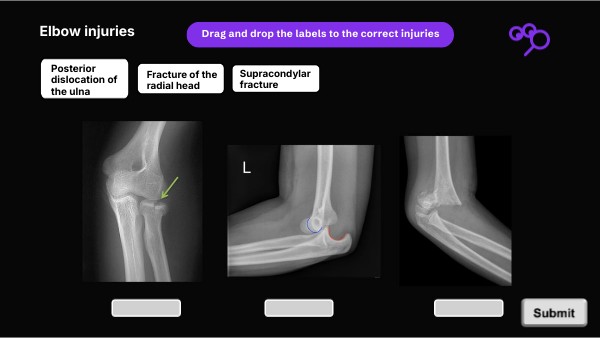

Drag and drop the labels to the correct injuries

Posterior dislocation of the ulna

Fracture of the radial head

Supracondylar fracture

Elbow injuries